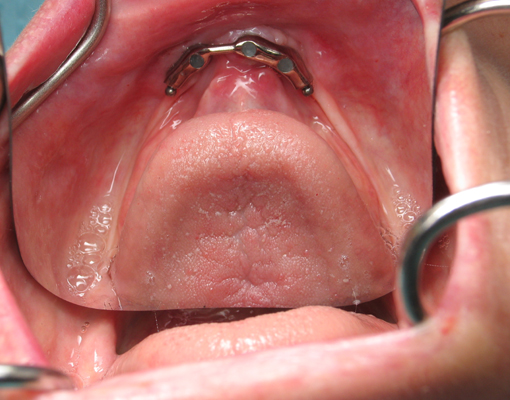

Teeth prepared for an overdenture - The denture

will fit over the metal-covered teeth that have been shaped by the

dentist.